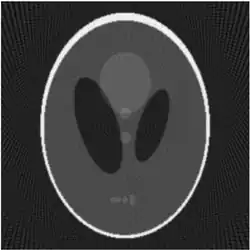

![]() |

| Fantasma de Shepp-Logan; Transformada de Radon; y Transformada de Radon inversa | ||